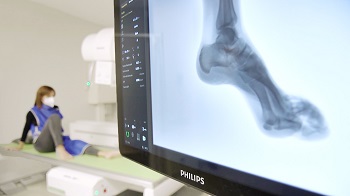

El sistema CombiDiagnost R90 1.1 de Philips abarca tanto estudios de radiologia simple como de radiologia compleja

Asepeyo ha instalado, en su centro asistencial Barcelona-Vía Augusta,  un sistema de fluoroscopia con control remoto combinado con radiografía digital avanzada, el CombiDiagnost R90 1.1 de Philips. El equipo permite abarcar estudios, tanto de radiología simple como de radiología compleja, en una misma sala, ofreciendo más comodidad y seguridad al paciente. Esta nueva release 1.1 del equipo Philips, es la primera que se instala a nivel global.

“El equipo proporciona mayor comodidad porque no es necesario ir moviendo al paciente, sino que es el propio aparato el que realiza los movimientos, y mayor seguridad porque evita la reiteración de exploraciones radiológicas, disminuyendo la dosis de radiación recibida por el paciente”, asegura el doctor Manel Vázquez Quintas, director de Traumatología de Asepeyo.

Las funciones de radiología digital del equipo Philips permiten a Asepeyo la realización de diagnósticos fiables con alta calidad de imagen. Como señala el doctor Vázquez, la tecnología digital “nos permite una mejor calidad de imagen, mayor rapidez, la conservación de los estudios en un formato digital y, por tanto, es un avance muy importante en la calidad asistencial que perseguimos”.

“Esta tecnología es muy útil porque podemos conseguir varias proyecciones con un importante ahorro de radiación para el paciente, y nos aporta un diagnóstico mucho más fiable”, apunta la enfermera Estecha. Esto se debe a que el sistema permite gestionar las dosis de radiación, una herramienta de la que se benefician tanto los pacientes, como el personal sanitario.